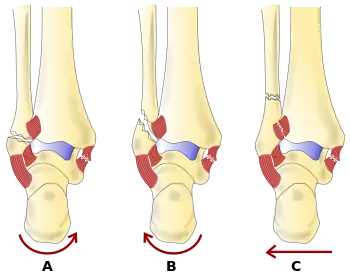

A triplane fracture of the ankle as seen on plain X-ray

A triplane fracture of the ankle as seen on CT

- Triplane fractures are a special type of fracture that involves the immature skeleton. It has a coronal plane in the metaphysis, an axial plane in the physis, and a sagittal plane in the epiphysis.[14]